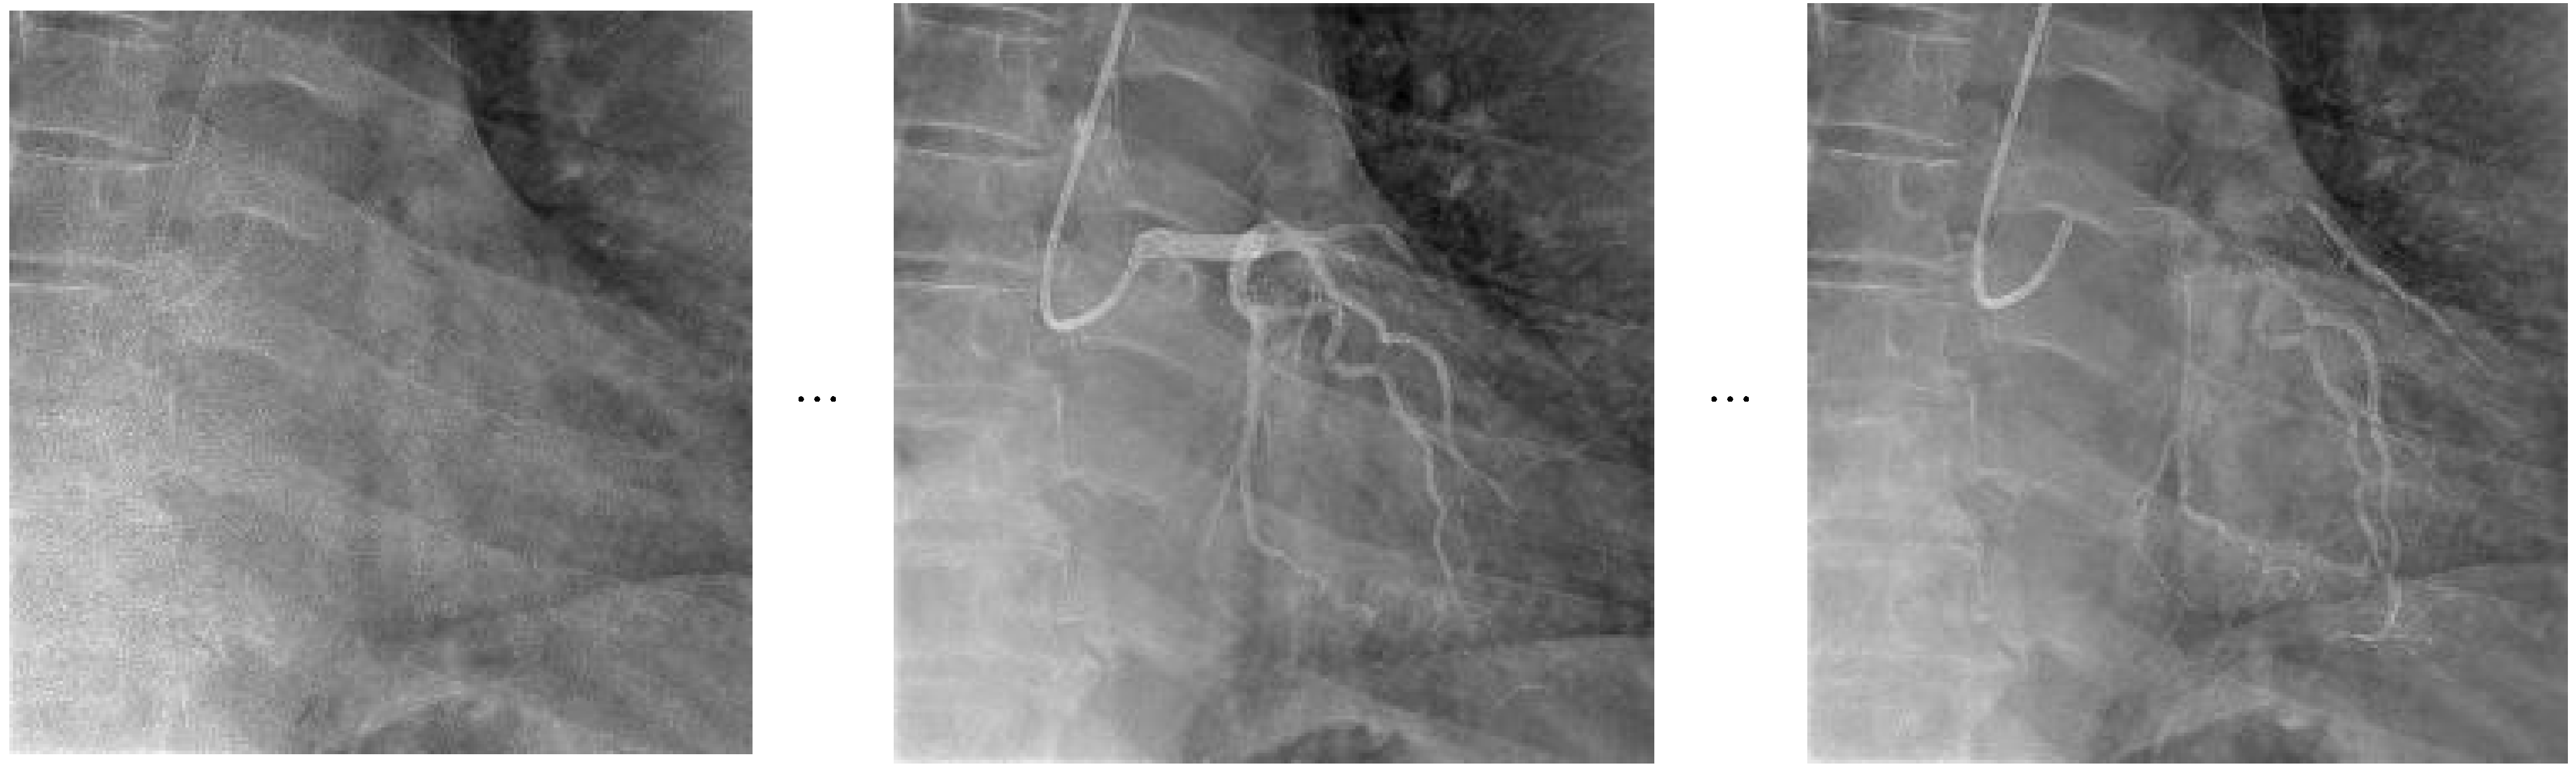

The structural components of the Video Swin Transformer, along with its hierarchical attention mechanism and shifted window operations, are depicted in Figure 3 as a block diagram tailored for video-based action recognition applications.

The frame sampling strategy utilized in the Video Swin Transformer, which focuses on extracting consecutive frames to effectively capture detailed temporal dynamics, is presented in Figure 4 as a visual representation.